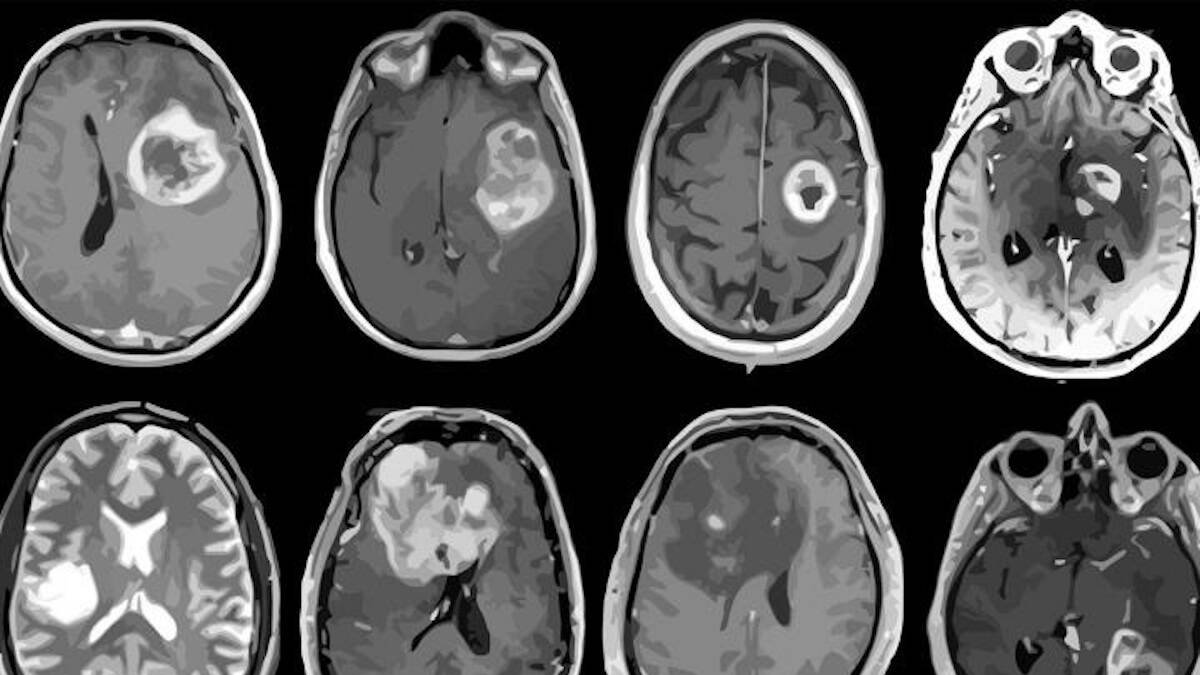

Según datos proporcionados por la Sociedad Española de Neurología (SEN) con motivo de la celebración este jueves del Día Internacional, cada año se diagnostican en España más de 5.000 nuevos casos de tumores cerebrales. Representan aproximadamente el 2 por ciento de todos los cánceres diagnosticados en adultos y el 15 por ciento en niños.

En los últimos años, se ha observado un incremento en el número de casos de tumores cerebrales, debido principalmente a la mejora de las técnicas de imagen, lo que ha permitido perfeccionar su diagnóstico, y al progresivo envejecimiento de la población. Estos tumores, que abarcan más de 120 tipos en el sistema nervioso, presentan un pico de aparición en la edad pediátrica y muestran un aumento progresivo con la edad en adultos, alcanzando su máximo de incidencia entre la sexta y la séptima década de la vida.

Se estima que en la actualidad hay alrededor de 20.000 personas en España que padecen algún tipo de tumor cerebral, ya sea clasificado como primario (originado en el cerebro) o como metastásico (originado en otras partes del cuerpo y diseminado al cerebro).